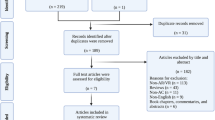

The human white matter pathway network is complex and of critical importance for functionality. Thus, learning and understanding white matter tract anatomy is important for the training of neuroscientists and neurosurgeons. The study aims to test and evaluate a new method for fiber dissection using augmented reality (AR) in a group which is experienced in cadaver white matter dissection courses and in vivo tractography.

Fifteen neurosurgeons, neurolinguists, and neuroscientists participated in this questionnaire-based study. We presented five cases of patients with left-sided perisylvian gliomas who underwent awake craniotomy. Diffusion tensor imaging fiber tracking (DTI FT) was performed and the language-related networks were visualized separated in different tracts by color. Participants were able to virtually dissect the prepared DTI FTs using a spatial computer and AR goggles. The application was evaluated through a questionnaire with answers from 0 (minimum) to 10 (maximum).

The European Low-Grade Glioma Network (ELGGN) workshop group, consisting of 15 experts with neurosurgical, neurolinguistic, and neuroscientific experience, met in December 2019. Since the attending ELGGN members were experienced in cadaver and in vivo fiber dissections, we decided to evaluate AR and its potential for virtual fiber dissection courses with this target group.